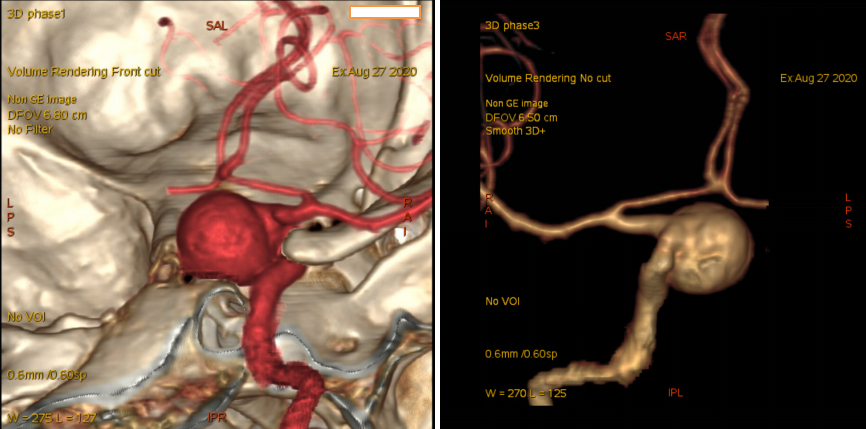

今日与大家分享的是《正海-妙术视界》第二百三十三期,由南京脑科医院何升学主任医师带来的Dolenc入路和颈部颈动脉逆向抽吸技术处理床突旁大动脉瘤2例,欢迎观看、分享。

入院后予完善头颅DSA检查提示左侧颈内动脉眼动脉段动脉瘤;头颅MR提示脑内多发陈旧梗死,告知其介入栓塞、开颅夹闭等治疗方式、利弊、风险及费用等,患方商量后决定行开颅动脉瘤夹闭术。

头颈部CTA

术前DSA